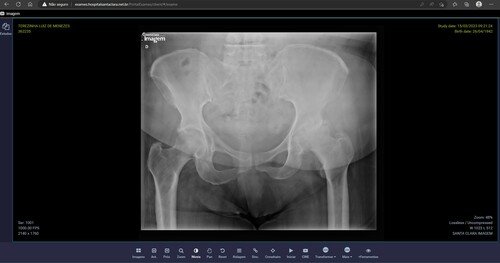

Sinto muita dor na minha perna, no quadril, preciso colocar uma prótese no quadril, tomo remédio, mais não melhora, somente a cirurgia vai resolver meu problema.

Imagens abaixo do Raio X e Orçamento.